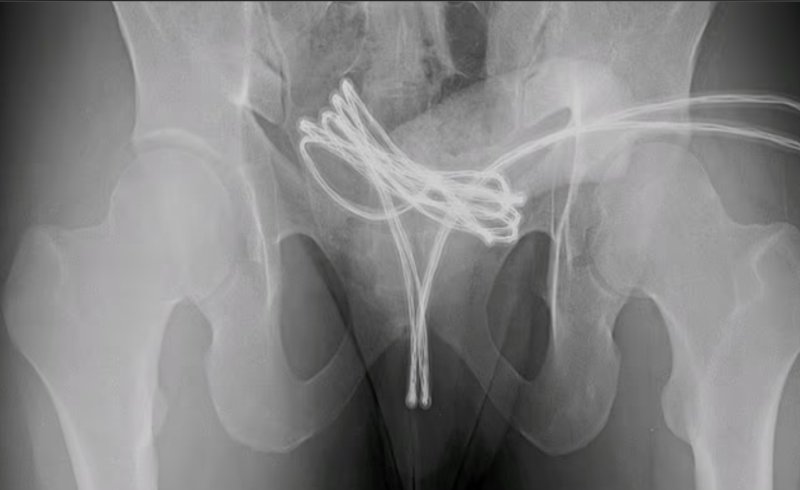

검사 결과 그는 고리 모양의 케이블을 요도로 깊숙이 밀어 넣어 방광으로 들어간 뒤 끼어 버린 것으로 나타났다.

의료진은 "처음에 직원들이 손으로 케이블을 잡아 당기려고 했지만 실패했다"며 "마취를 시키고 요도에 특수도구를 삽입해 케이블을 빼낼 수 있었다"라고 말했다.